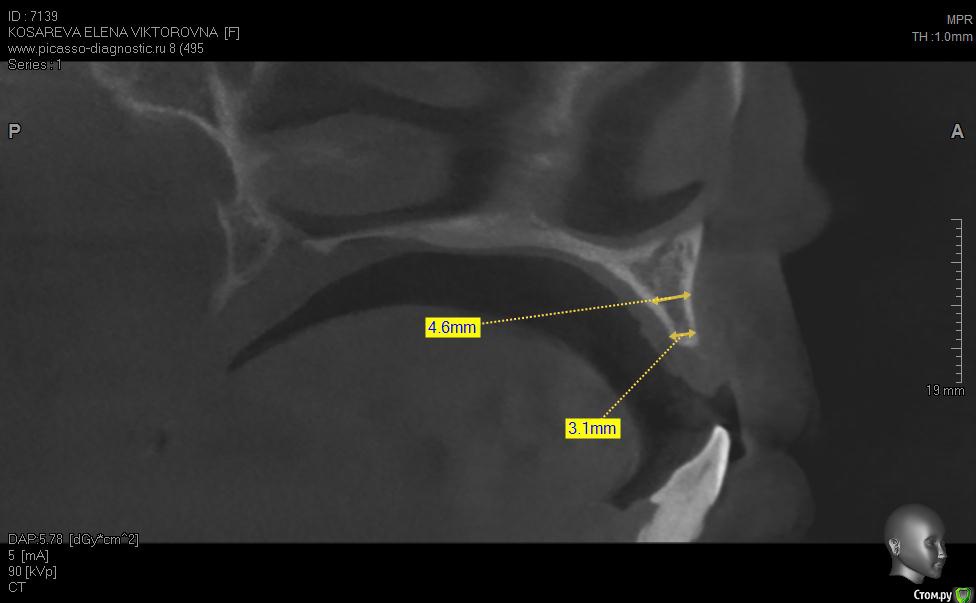

Уважаемые коллеги помогите пож с планом лечения, хотелось бы услышать ваши планы лечения,

пациент хочет красивую улыбку и импланты, клыки трогать категорически отказалась как опоры под временные на период интеграции имплантов